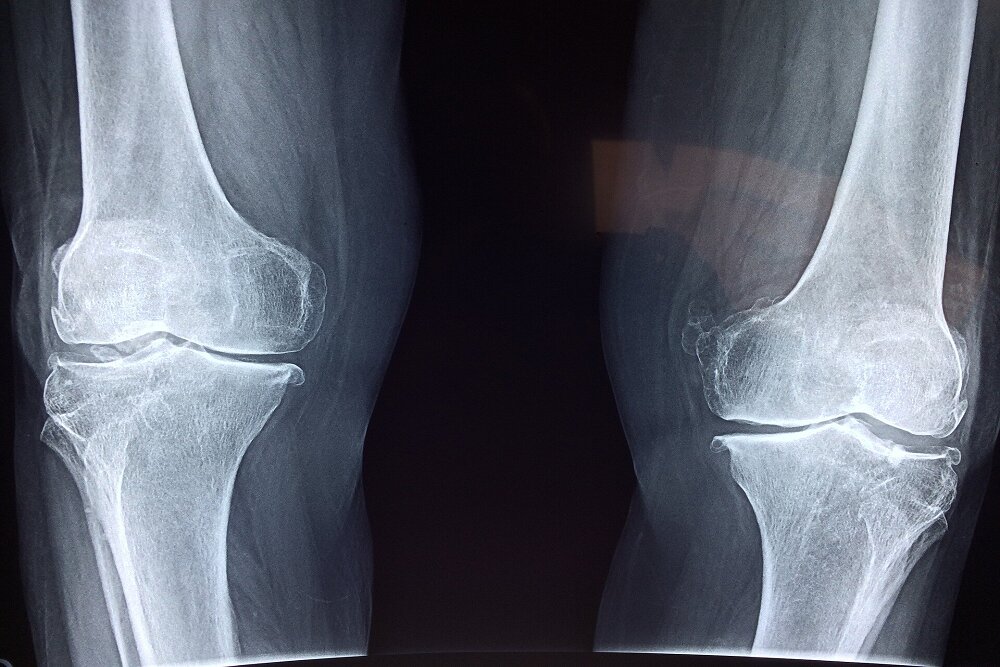

آسیب به استخوانها

نخستین نگرانی، تاثیر منفی بر سلامت استخوانهاست. مصرف نوشابه و الکل هر دو با کاهش تراکم مواد معدنی استخوان و افزایش خطر شکستگی مرتبط است. مصرف نوشابه بهدلیل وجود اسید فسفریک میتواند تعادل کلسیم و فسفر را بر هم بزند و خطر شکستگی لگن را افزایش دهد. مصرف الکل نیز با کمبود کلسیم، اختلالهای کبدی و کاهش ویتامین دی همراه است که همگی به تضعیف استخوانها منجر میشوند.